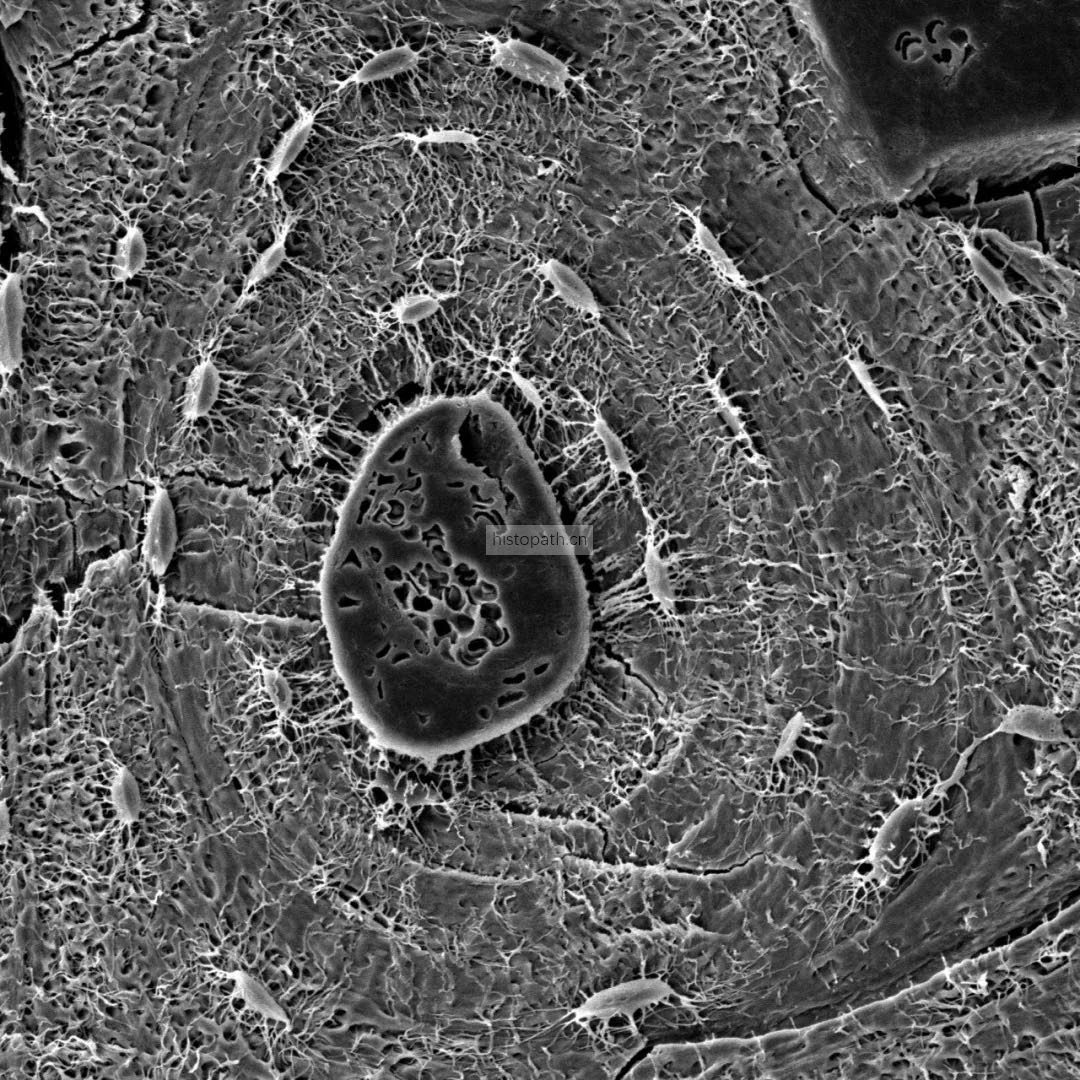

透射电镜样本准备方法及要求:

①  1-3min内取样,取样组织2mmX2mm大小,尽量薄。如来不及修整组织大小可先于电镜固定液内固定半小时左右待组织变硬以后再修整组织进行后固定。超出此范围后组织会无法完全固定,后续实验无法完成,务必请重视此过程

②  取材时尽量精确到需要观察的目的部位(如观察肾小球取肾皮质;观察胰岛取胰岛丰富的胰尾;皮肤,肠胃等在固定液中易打卷的组织可将组织粘在滤纸上进行固定)。

③  取材时一定注意避免镊子挤压等机械损伤,刀片要锋利避免挫伤组织。

④  组织取下后立即投入电镜固定液内室温避光固定2h,再转移至4°保存,4°冰袋运输,在保存和运输过程中固定液切勿冷冻结冰。4°时样本可保存1个月左右